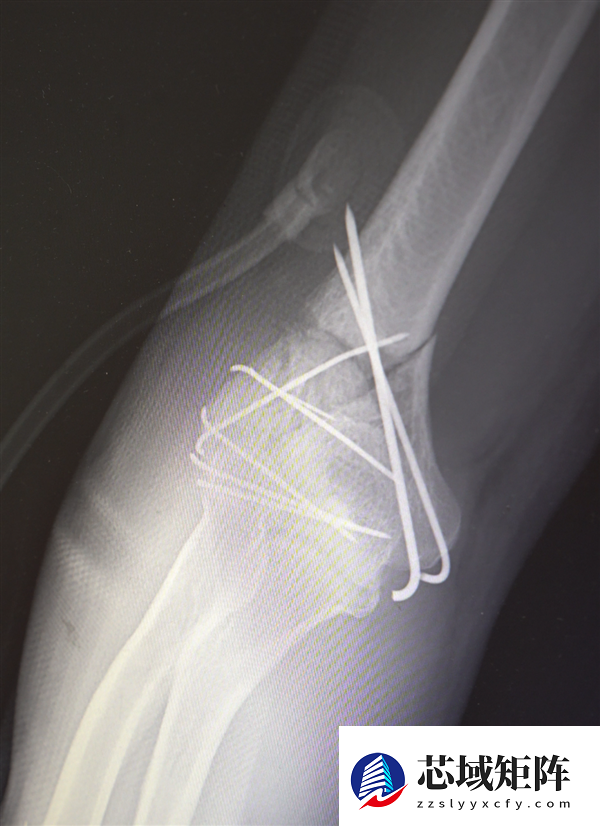

鉴于男子多处骨折,其中最严重的当属右肘部C3型粉碎性骨折,关节面及髁上严重粉碎(碎成了七块),肘关节易粘连,复位固定难度极高。

最终医疗团队采用了“拼古董”式复位固定技术,就像修复一件珍贵的古董瓷器,先拼接大块骨块再贴合小块,先后进行了两次手术。

部分手术后拍摄的影像